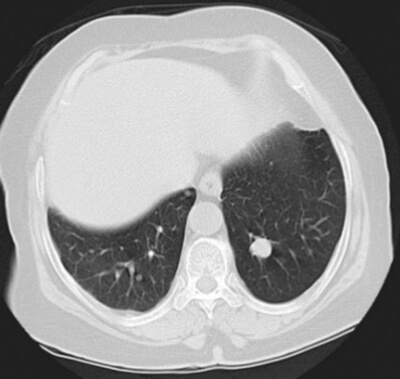

- The patient had the test shown in Figure 2 in clinic as part of their postoperative follow-up. What does it show?

5. This is a CT scan image of the chest demonstrating a lesion in the left upper lobe. This lesion would be highly suspicious of tumour recurrence given this patient’s history.

6. Assuming this lesion represents metastatic disease, the management options are dependent on a number of factors: patients’ comorbidities, renal function and performance status. First-line treatment options include platinum-based chemotherapy in patients who are fit. Programmed cell death protein 1 (PD-1) and programmed death ligand 1 (PD-L1) inhibitor immunotherapy treatment can be used in patients who progress on platinum-based treatments or in those who are ineligible for platinum-based first line treatments.